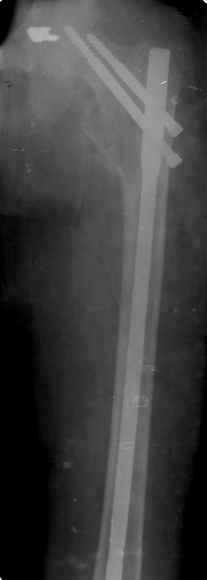

Re: Патологический перелом/ рецидив костной кисты

Спасибо за все ответы и комментарии по этому вопросу. Неделю назад мы прооперировали пациентку. Представляем ее снимки.